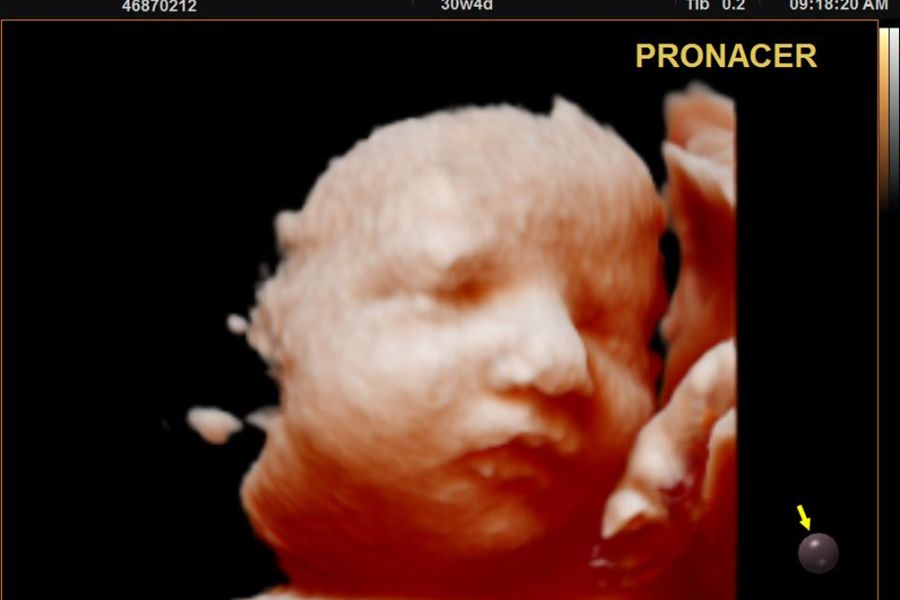

Ecografía 4D